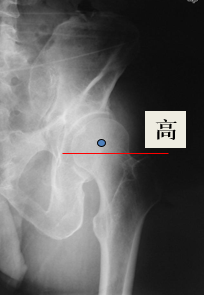

确定正常侧髋关节的旋转中心镜像至患侧:

确定股骨颈截骨线对侧髋关节正常,可以对侧为参照

-镜像确定在患侧的截骨高度